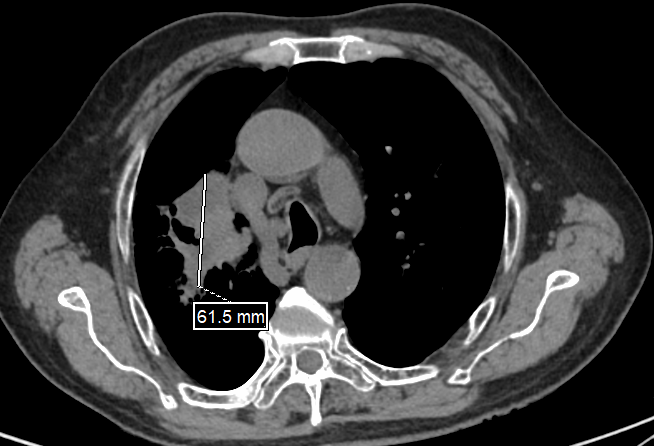

这个比“拳头”还大的病灶让病情变得棘手,不仅侵犯邻近结构且存在区域淋巴结转移,还包裹了周围血管和支气管,且靠近肺门,直接手术风险高、难度大。但胡大爷及家人手术意愿非常强烈。为此,黄建主任团队审慎评估后,决定采用“新辅助治疗”策略:即先通过药物治疗缩小肿瘤、控制潜在微转移,再行根治性手术,并创造保肺条件。方案确定后,胡大爷积极配合治疗。经三个周期的“免疫治疗+化疗”治疗后,复查结果显示胡大爷肺上的肿瘤缩小至4.3cm×6.1cm,达到“可手术切除”标准。

(新辅助治疗后CT)